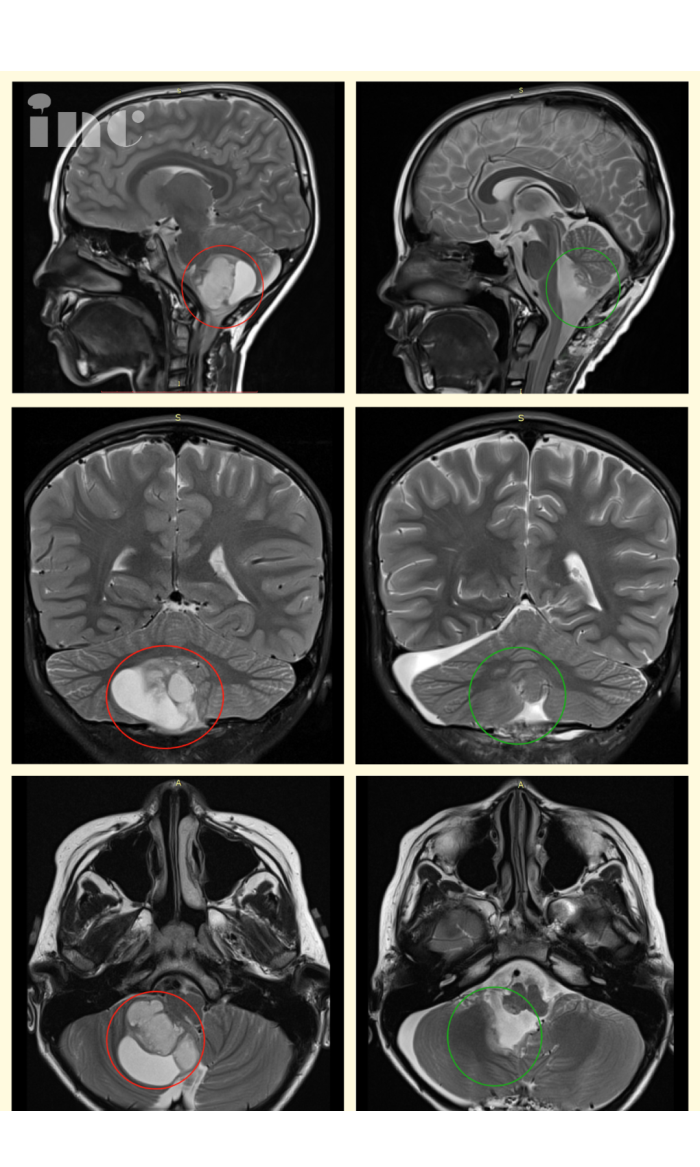

4.7岁辰辰,较大胶质瘤累及脑干

7岁男孩辰辰,被确诊较大胶质瘤累及脑干,手术难度较大,可能面临瘫痪的风险。为救孩子的命,疫情之下,父母带辰辰远赴德国INI医院找到INC巴特朗菲教授手术。较终,晨晨的脑干胶质瘤得到全切,现在的辰辰已经重回健康,恢复跟正常小孩无异。

“因为当时我们在无锡人民医院的时候就是有一个神经外科的主任,他在中国的神经外科学位协会里面是前26的,是以他的程度,他看了我们的报告之后,强烈建议我们,他的角度是强烈建议我们去国外找巴教授做这个手术,当时我们自己综合考虑了小孩的这个以后的这种情况,我们就决定还是把他送到国外去 ,找巴教授去做这个手术。对手术效果满意,从我们到达德国之后,到小孩进手术室的那一刻,我心里对教授的信任,基本都是教授的,小孩上手术台之后,到二天从重症监护室下来,我的心里对小孩未来的生活状况也是有信心的。”——辰辰妈妈